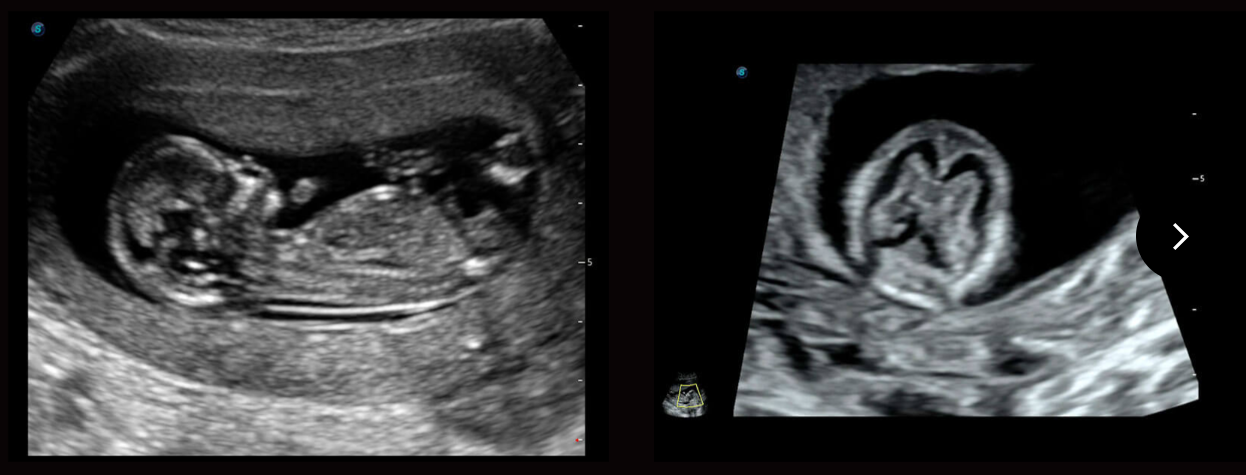

S-Fetus

Tự động phát hiện và đo 16 thông số thai nhi bằng trí tuệ nhân tạo AI trong quy trình siêu âm sản khoa.

Tự động thu thập mặt phẳng tiêu chuẩn (có sẵn trên BPD/AC/HC/FL).

Sinh trắc học và báo cáo tự động.

Đã xác minh hơn 10000 trường hợp với độ chính xác 98%.

Auto OB

Tự động OB giúp siêu âm thai nhi nhanh chóng và hiệu quả. Kết quả nhất quán làm giảm sự thay đổi phụ thuộc vào người dùng.

Auto NT

Tự động NT cung cấp các phép đo độ mờ da gáy bán tự động, tiêu chuẩn hoá trong hình ảnh 2D, giúp giảm sự phụ thuộc của người vận hành và kết quả.

Auto Face

Tự động nhận diện khuôn mặt

Tự động tối ưu hóa khuôn mặt thai nhi 3D

Tự động loại bỏ tình trạng tắc nghẽn ở phía trước khuôn mặt thai nhi

Nhận dạng chính xác cấu trúc giải phẫu khuôn mặt thai nhi

Tương quan hình ảnh không gian-thời gian (STIC): Đạt được khả năng thu thập nhanh chóng và phát hiện chuyển động các cấu trúc giải phẫu của thai nhi, giúp chẩn đoán bệnh tim bẩm sinh ở thai nhi.